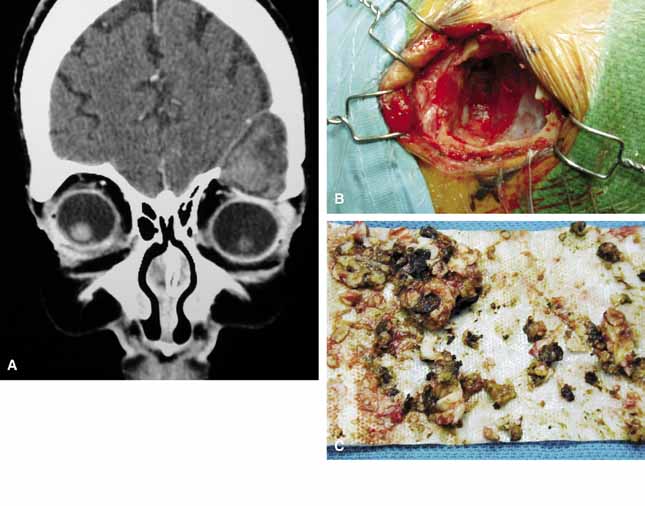

Fig. 3 In a coronal image of a computed tomogram, an intradiploic dermoid cyst is shown to involve the superior orbital rim and roof of the left orbit displacing the globe downward (A). The intraoperative cavity (B) of the cyst is observed with the evacuated keratin debris shown (C).

It is often cosmetic considerations that prompt the parents of an affected child to seek treatment. These cysts enlarge as the child grows and the possibility of accidental traumatic rupture is ever present. In adults, mass effect or periorbital inflammation due to leakage of cyst contents may prompt medical attention and surgical removal (Fig. 4).5,10